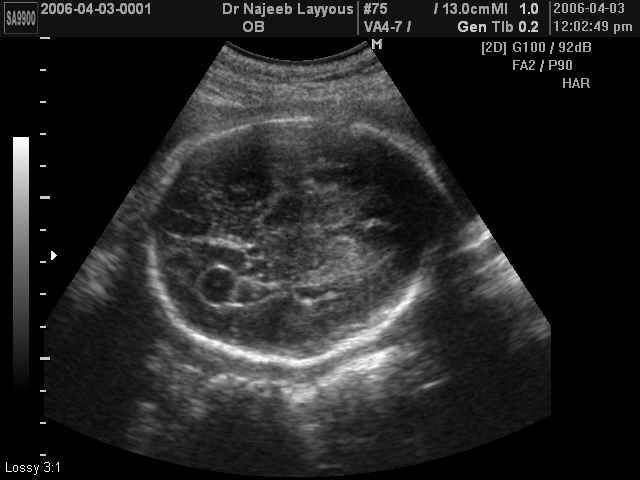

صور طبية للحمل بجهاز الالتراساوند | الدكتور نجيب ليوس